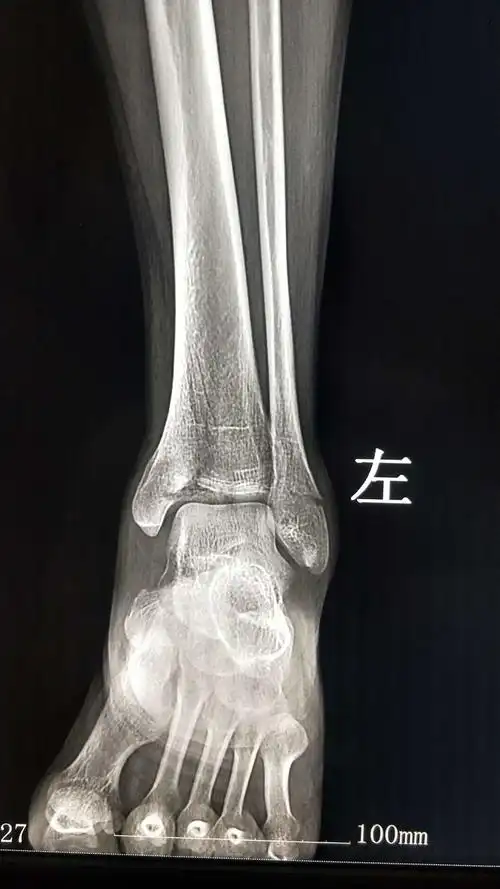

周小珍脚踝3.jpg

x射线踝关节.

慎扭伤至今未愈 x 女,36岁,7月前右踝关节不慎扭伤,当时并未拍片

踝关节侧位x线片